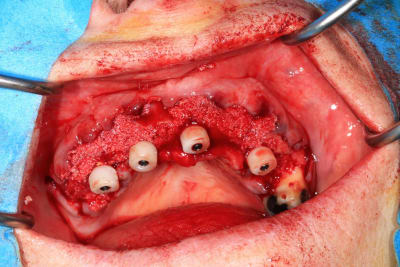

Le cas N°2 en images reelles :)

Guide métal avec support clavette, os assez fin : il est prévu un sticky bone complet : donc : lambeau avant extraction, positionnement du guide base et forage des clavettes, positionnement du guide implant, pose des piliers MU, controle des axes prothétique avec le guide pilier, collage des piliers prov sur le bridge a armature métal, occlusion nickel, sticky bone et PRF, sutures suspendues.

Voilà les photos du cas , avec un peu de retard.

06C757A0-0679-4A5E-A2AD-9E867A3CB080.jpeg

65672A94-F454-46C1-A2A7-47927485B543.jpeg

143DCC8C-EA6F-4EE5-9915-F12A33C377B9.jpeg

F8362BF2-81BC-455C-BFD0-A9FE9451F3F4.jpeg

91CE34AF-EDB6-436D-8B12-726F81FC0CB1.jpeg

4060EC60-1F78-4778-B0E3-5FE470671FDF.jpeg

F4ECCBAA-30DE-407C-AAD1-02D226210CC9.jpeg

C4C89A41-3628-4190-A864-AFFC591089BF.jpeg